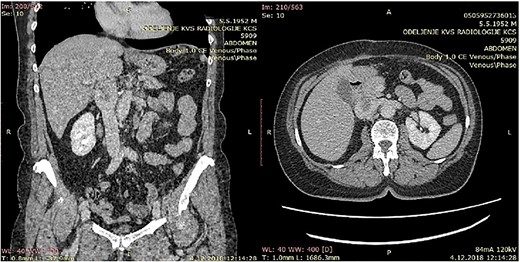

CT of the abdomen that shows a retroperitoneal tumor mass that involves IVC above the renal and under the liver veins.

All five patients underwent surgical resection of primary LMS. A majority of patients had involvement of only their suprarenal IVC (three patients; 60%). Two patients (40%) had tumor involving infrarenal segment IVC (I segment). IVC was reconstructed using Dacron grafts in all patients (five patients; 100%). A bypass was done on the left hepatic vein of one patient, while the other two patients required reimplantation of the renal veins directly into the graft (while one of them, the other to the left of the RV). Additional organ resection was required in one patient (20%): in whom cholecystectomy was performed and partial liver resection due to metastasis in the left lobe of the liver. The mean total duration of surgery was 212 minutes, and the average estimated blood loss was 1126 ml.

Because of previous reasons the diagnosis of the primary IVC LMS is often incidental. When symptoms are present, the computerized tomography (CT) or NMR are useful to confirm the presence of a tumor, its pattern of growth, relationship to the surrounding structures, and the presence of caval obstruction [10, 12]. In all five of our cases, MDCT angiography showed tumor of the IVC. The final ultimate diagnosis, of course, is carried out using histopathological and immunohistochemical methods. The pathognomonic findings of LMS are spindle-shaped tumor cells with positive markers for smooth muscle cells, vimentin, muscle actin, alpha-smooth-muscle actin, and desmin [13].